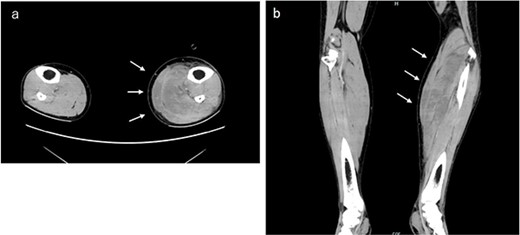

Immediately after surgery, he experienced numbness in the left lower leg that progressed to severe pain 3 h later. Plantar dorsiflexion of the ankle joint was possible, and the left lower leg was tense; however, the dorsalis pedis artery was palpable. Abnormalities in the lower leg diameter and color tone were not observed. Abnormally high muscle lactate dehydrogenase (1084 IU/L) and serum creatine kinase (CK) (23 571 IU/L) levels were observed 8 h postoperatively. His dark brown urine suggested myoglobinuria (not measured). Contrast-enhanced computed tomography (15 h after surgery) revealed no obvious lower extremity venous thrombosis; however, edema in the soleus and gastrocnemius muscles of the left lower leg suggested a diagnosis of left lower leg compartment syndrome (CS) (Fig. 1). Calf muscle pressure monitoring was not possible in our hospital; therefore, he was clinically diagnosed with WLCS.

Contrast-enhanced computed tomography examination of both lower limbs. Obvious venous thrombosis was not observed in the lower extremity vessels. Significant edema was observed in the soleus and gastrocnemius muscles of the left lower leg. (a) Horizontal and (b) coronal sections.